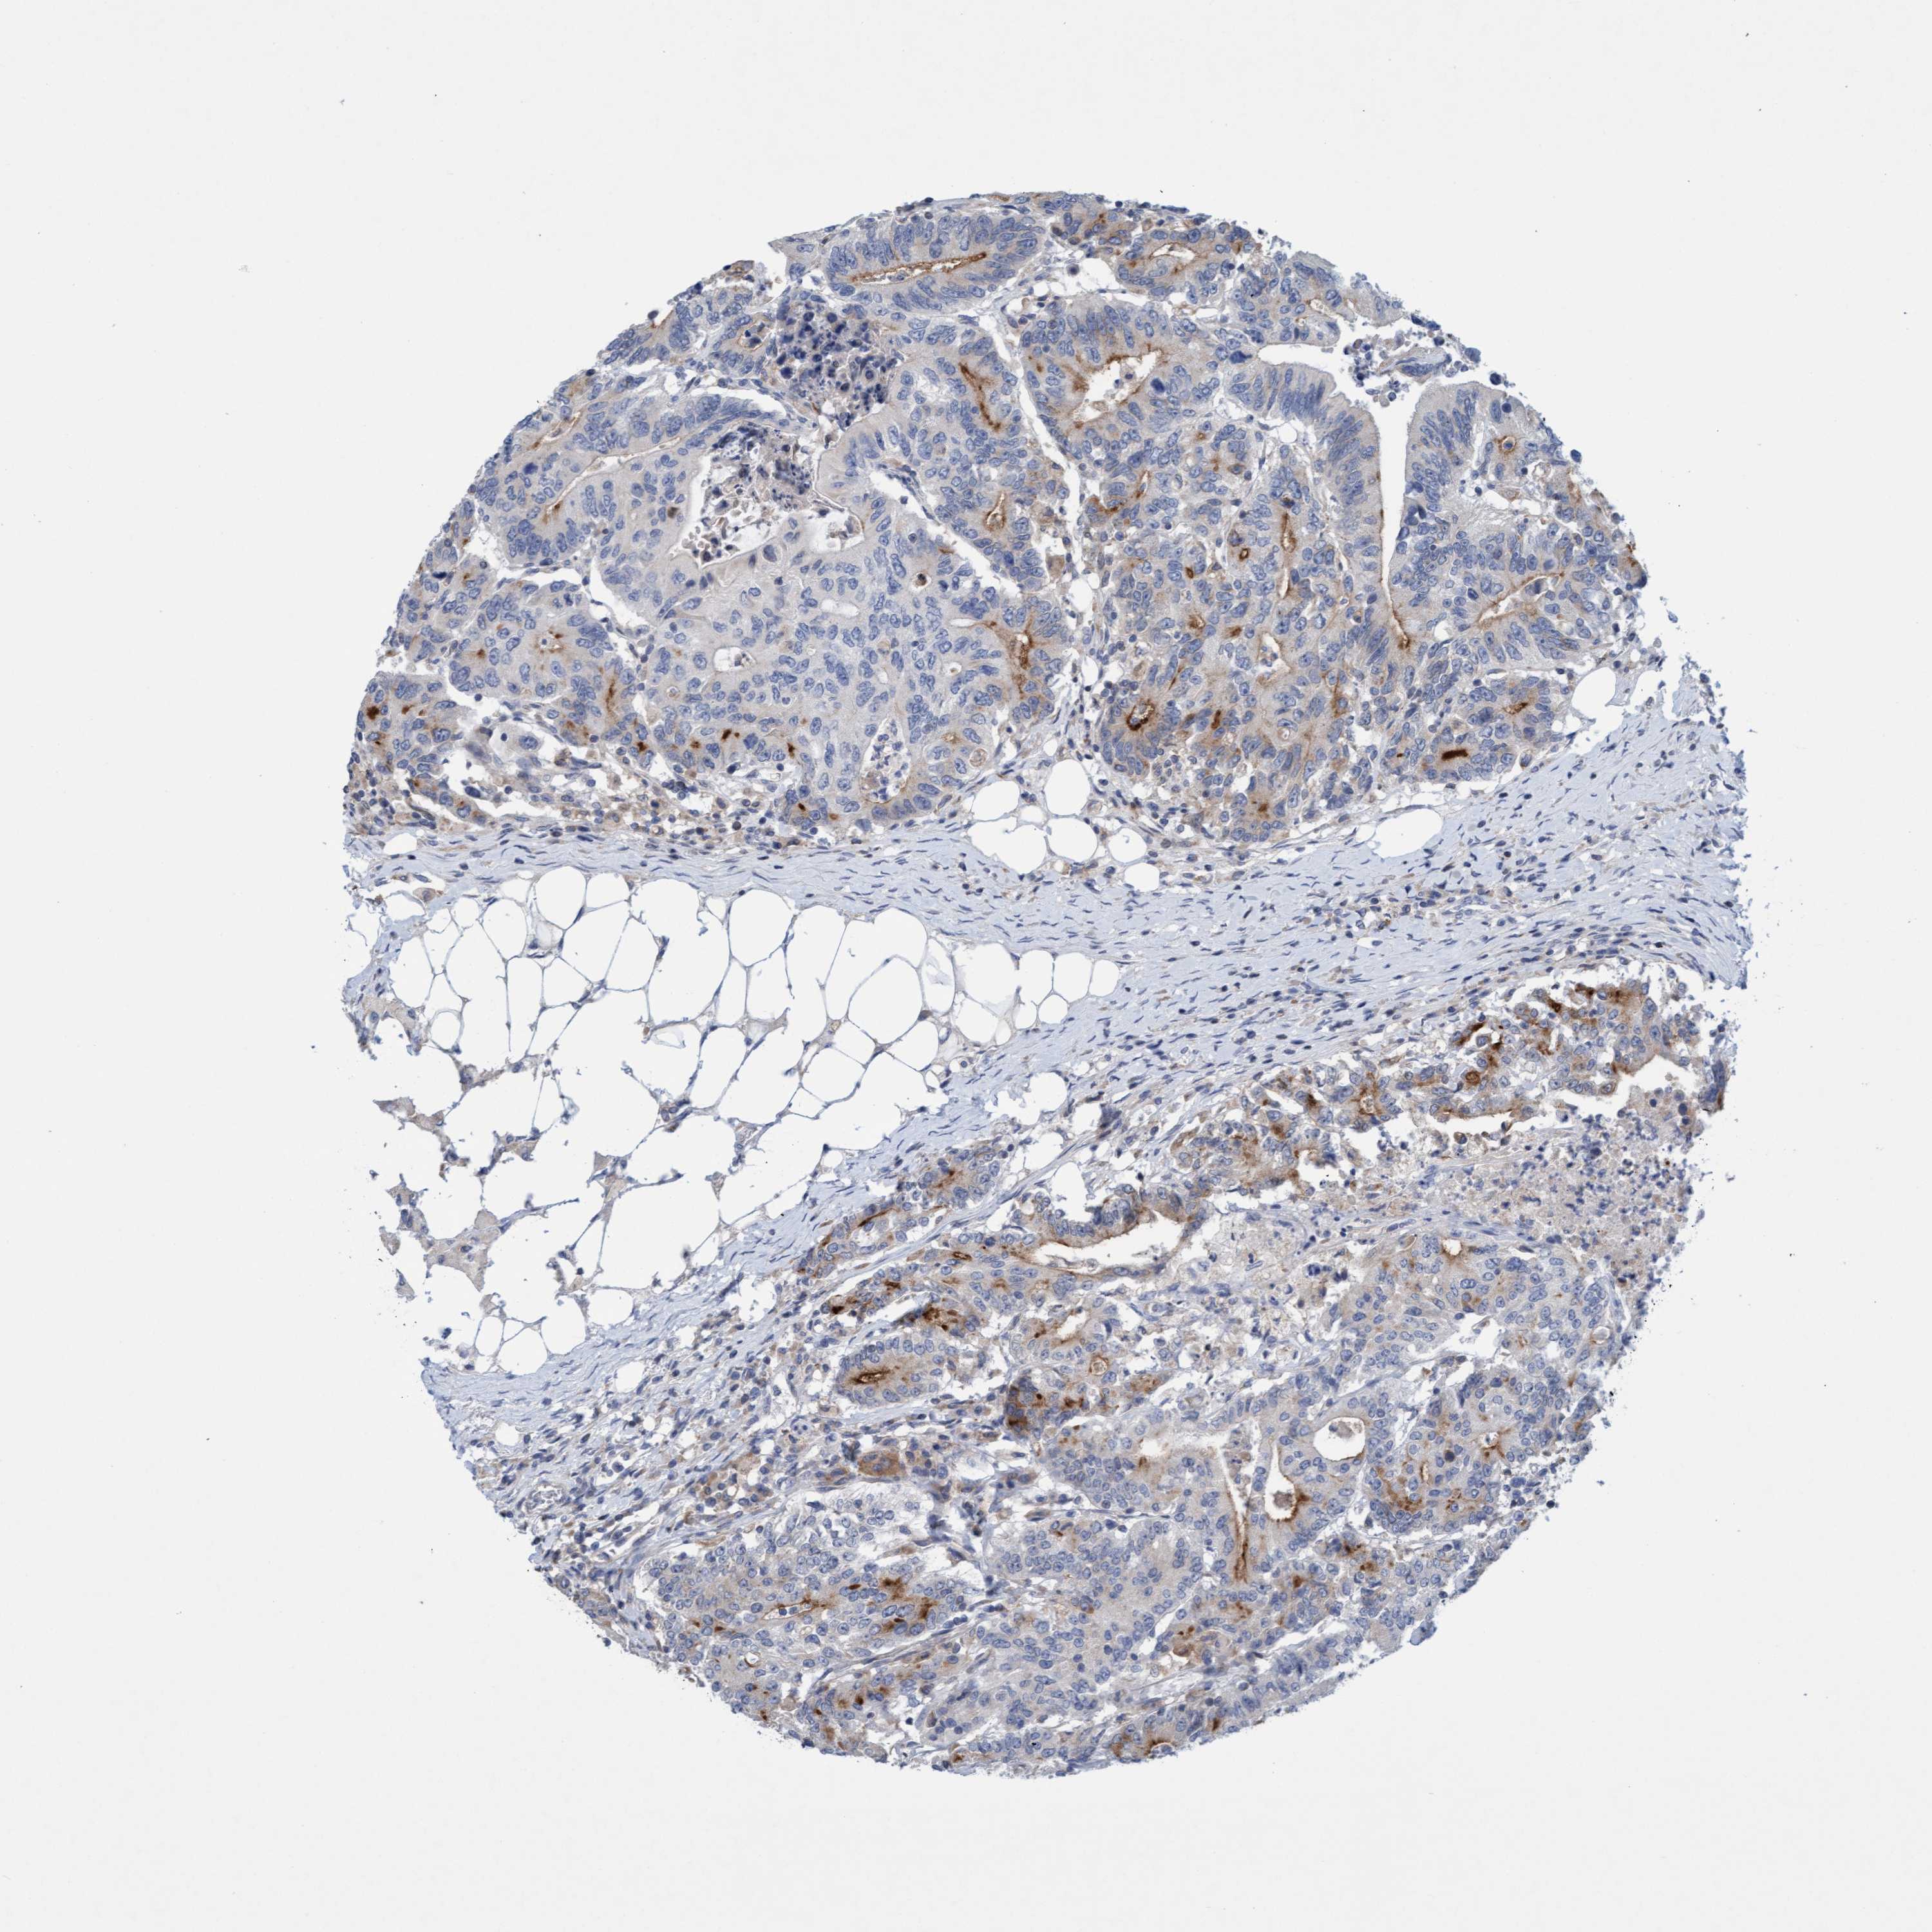

CANCER COLORECTAL CANCER Show tissue menu

Colorectal cancer

Human cancer

Colon adenocarcinoma